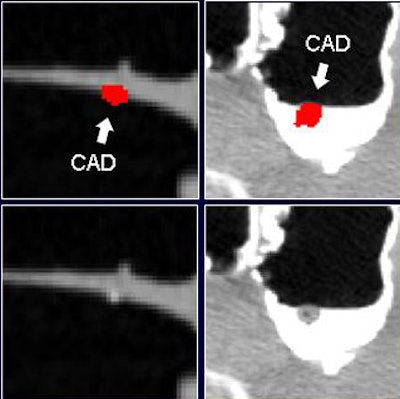

Among the false positives identified by the densitometric partial-volume enhancement method and the wall-connection analysis method, approximately 41% were caused by poorly tagged feces, with 30% caused by completely untagged feces. Most of the remaining false positives were caused by fecal residues that adhered to the bowel wall.

| Before the application of the densitometric partial-volume correction and wall-connection analysis (top row) in virtual colonoscopy data, CAD misinterprets residual fecal material as polyps. These false positives are eliminated after application of the two methods (bottom row). |